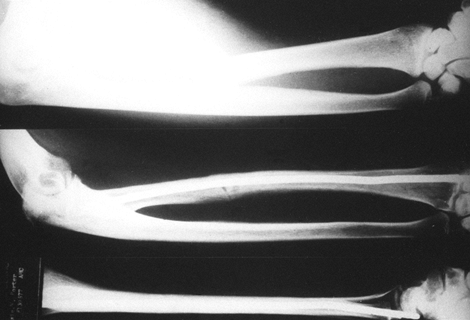

those that propagate from the distal third of the olecranon are

potentially unstable. The biceps and brachial muscles may cause

anterior subluxation of the radial head and displacement of the distal

fragment of the ulna. This adds a compressive force to the posterior

surface of the olecranon, making tension band wiring less effective (71).

Therefore, I recommend rigid internal fixation with interfragmentary

compression screws augmented by a neutralization plate. In some cases,

a reverse obliquity of the fracture line may result in a proximal

fragment too small for plate fixation. In this case, use an

intramedullary compression screw to prevent anterior subluxation (Fig. 16.12). Failure to recognize

this specific fracture pattern may result in unsatisfactory fixation.

![]() |

Figure 16.12. A:

A type III olecranon fracture in which the proximal fragment is insufficient for plating. Gross instability with anterior subluxation of the radius and ulna is noted at the time of surgery. B: Fixation using an intramedullary cancellous screw and tension band wiring. |